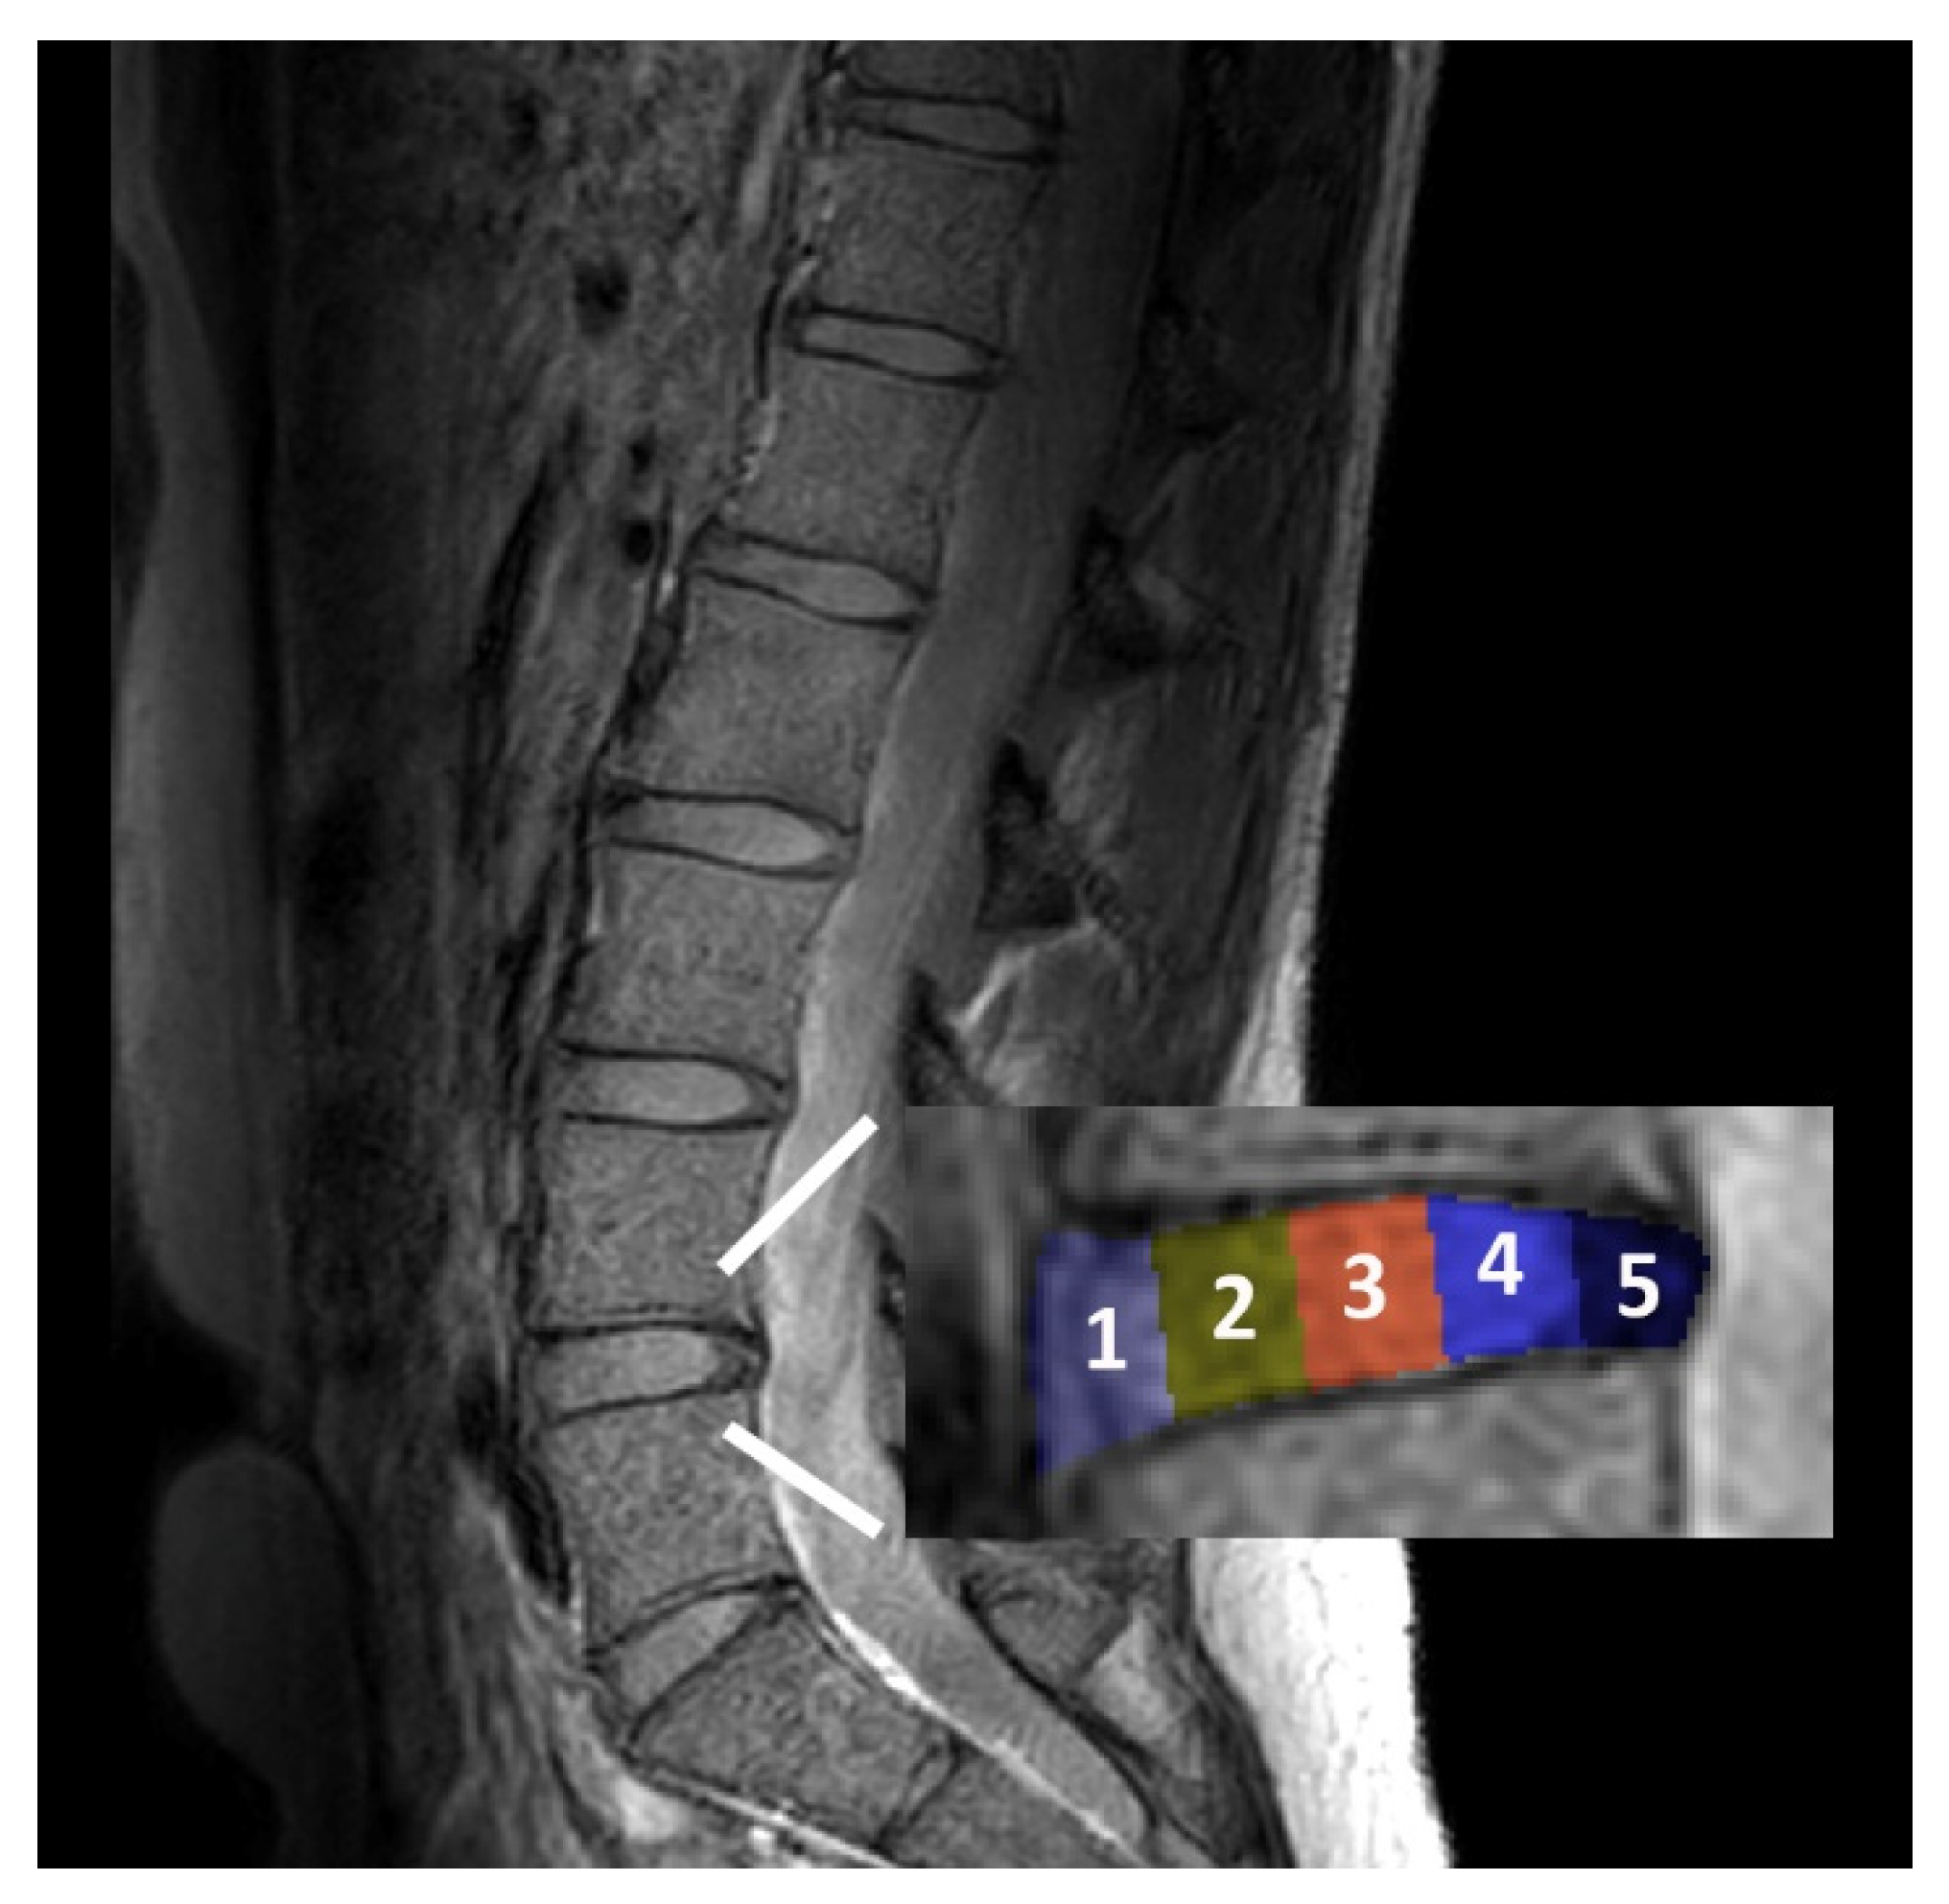

2.3. Image Analysis

- T2w imaging: For normalization, the ratio of the average T2w signal intensity (T2w-SI) in the nucleus to the average T2w-SI in the anterior and posterior subregions (annulus) was calculated.